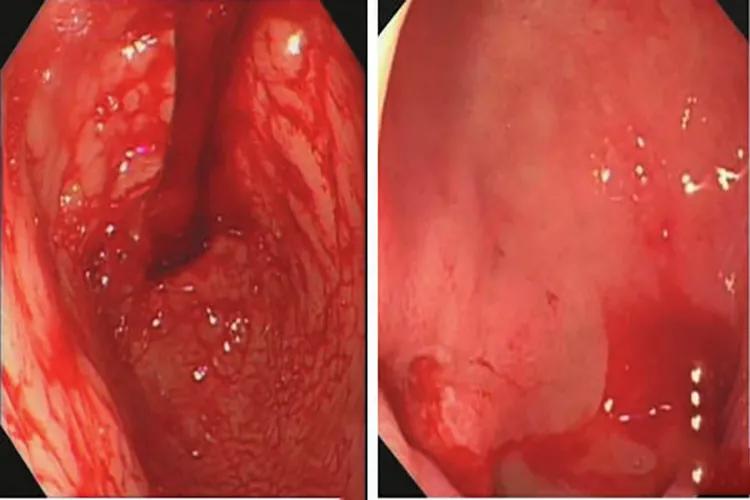

胃出血胃镜图